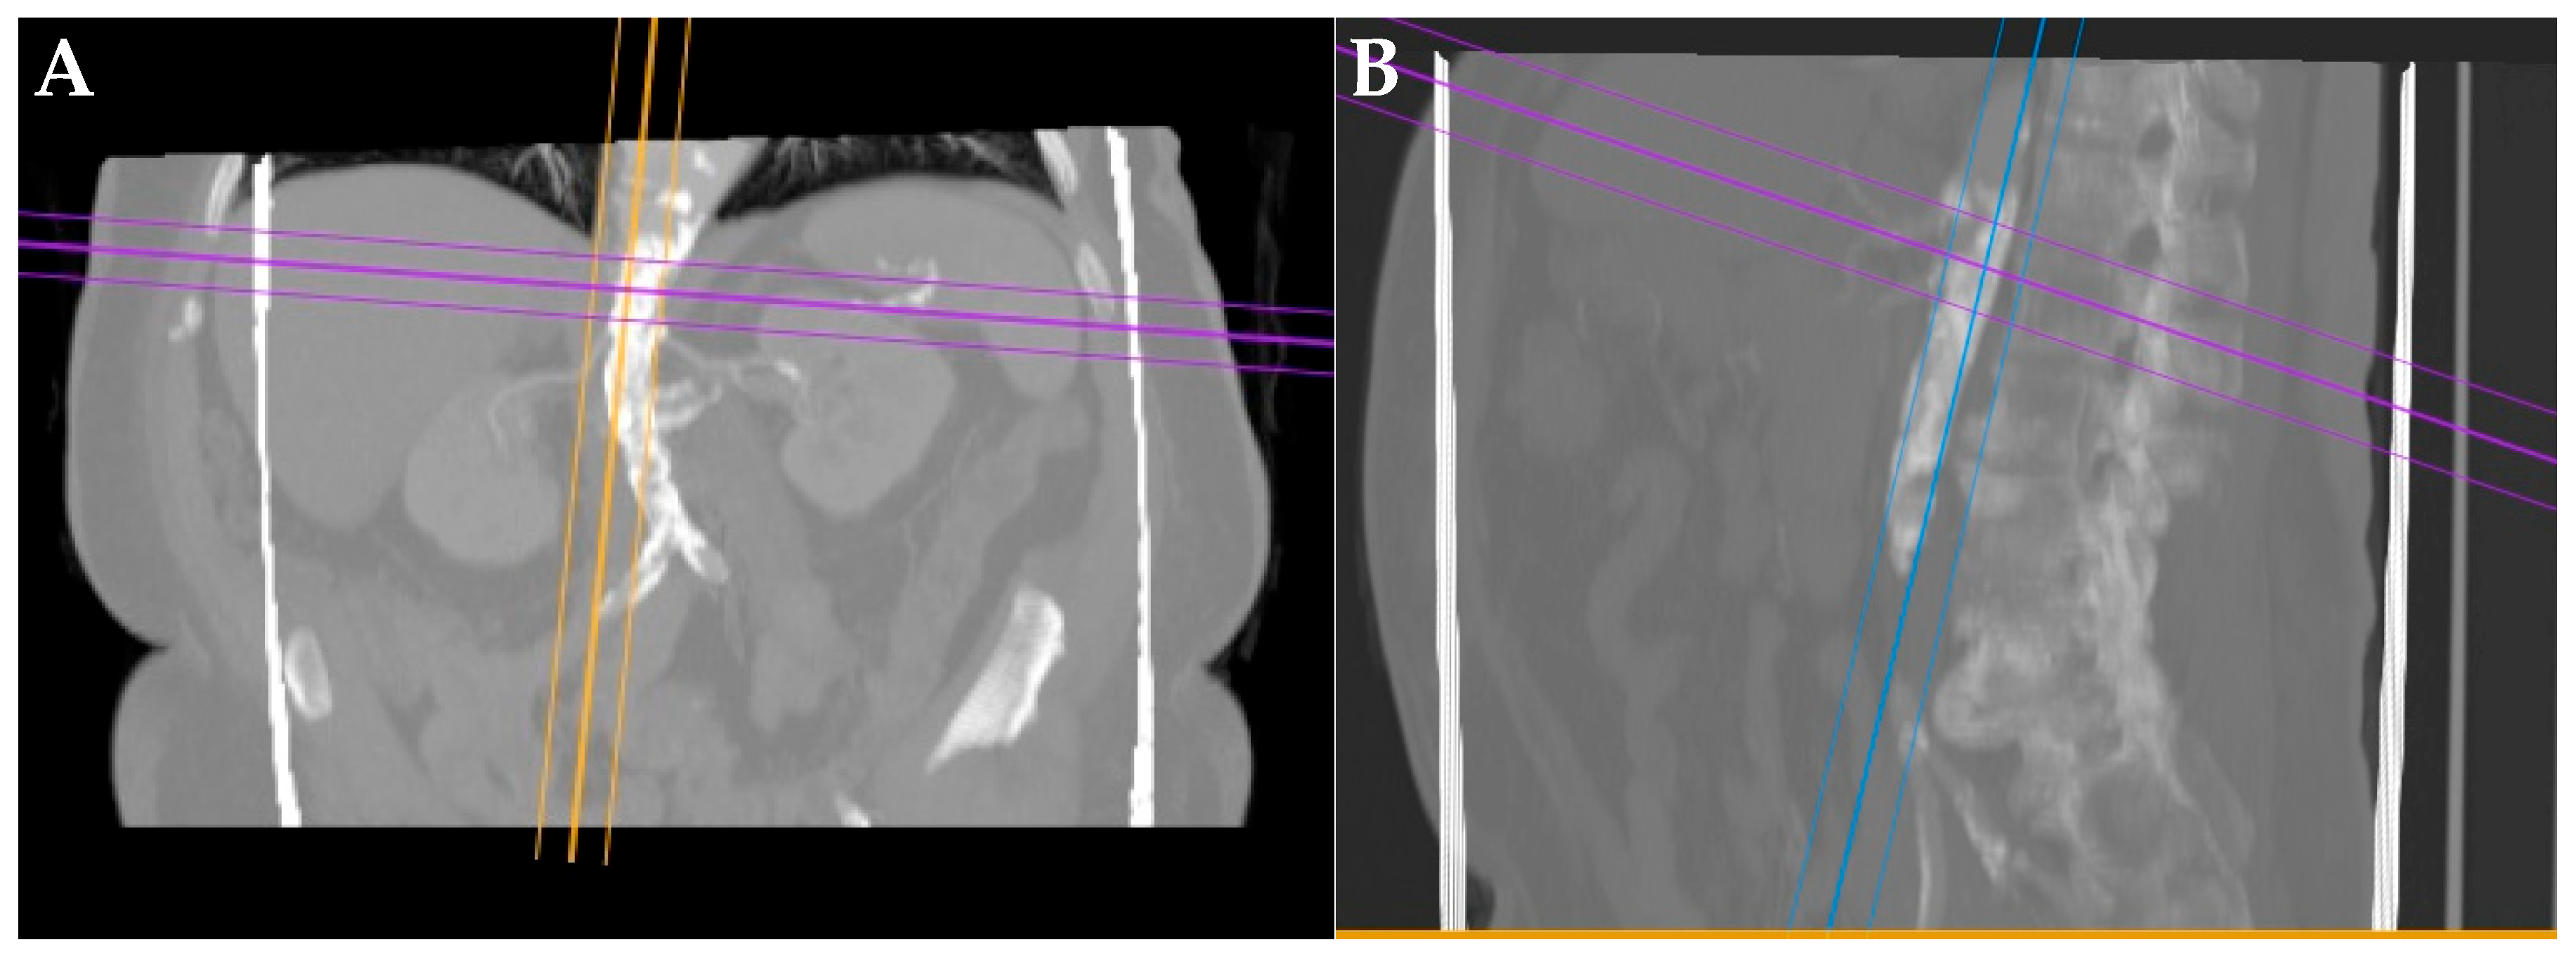

2.2. Preoperative Evaluation

2.3. Endovascular Procedure